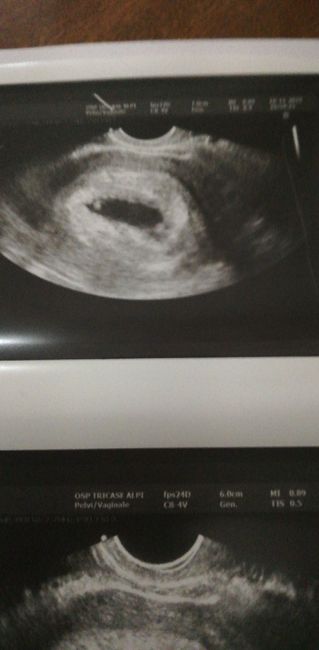

Buonasera a tutte vorrei chiedervi un parere sabato 9 ho avuto la temperatura a 36.5 e ho avuto delle leggere perdite di sangue il giorno dopo cioè domenica 10*la temperatura ha iniziato a. Rialzarsi fino a oggi che era 37.1 secondo il ritardo sono incinta di 8 settimane. Domenica 10 sono andata in pronto soccorso mi hanno fatta l ecografia ed era tutto normale si era sentito anche il battito e la dottoressa mi aveva prescritto degli ovuli che li sto prendendo ogni sera. A pomeriggio ho fatta un ecografia dove la mia ginecologa non li è piaciuta l ecografia perché era piccolo e kon ha voluto neanche farmi sentire il battito perché diceva che non si sentiva. Qualcuna di voi è passata in questa situazione? Secondo voi se avevo perso il bambino si sarebbe visto qualcosa e la temperatura non sarebbe già iniziata a scendere. L ecografia di stasera l ho fatta in uno studio privato invece l altra in ospedale può essere stata la macchina diversa Ecografia 1auesra e di stasera

Ecografia 2

Questa è di giorno 4 novembre Ecografia 3